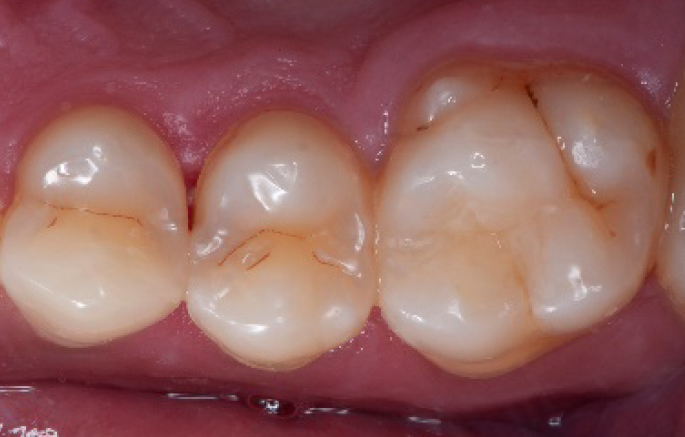

Transformation of a big class I into a small class I, using SDR® flow+ material in one increment up to 4 mm.

Step 10:

The situation after the application of SDR® flow+ material.

Step 11:

Occlusal surface restored using Spectra ST4 composite in shade A2.

Step 12:

The situation after rubber dam removal.